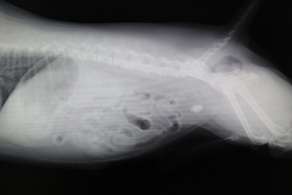

聴診器で心臓の雑音を調べたり、レントゲン検査で心臓の形態や肺の状態を確認したりします。

さらに超音波エコー検査では、カラードップラーを使い弁の動きや血液の流れから病気の進行の程度を把握します。病態にあった治療を選択していきます。